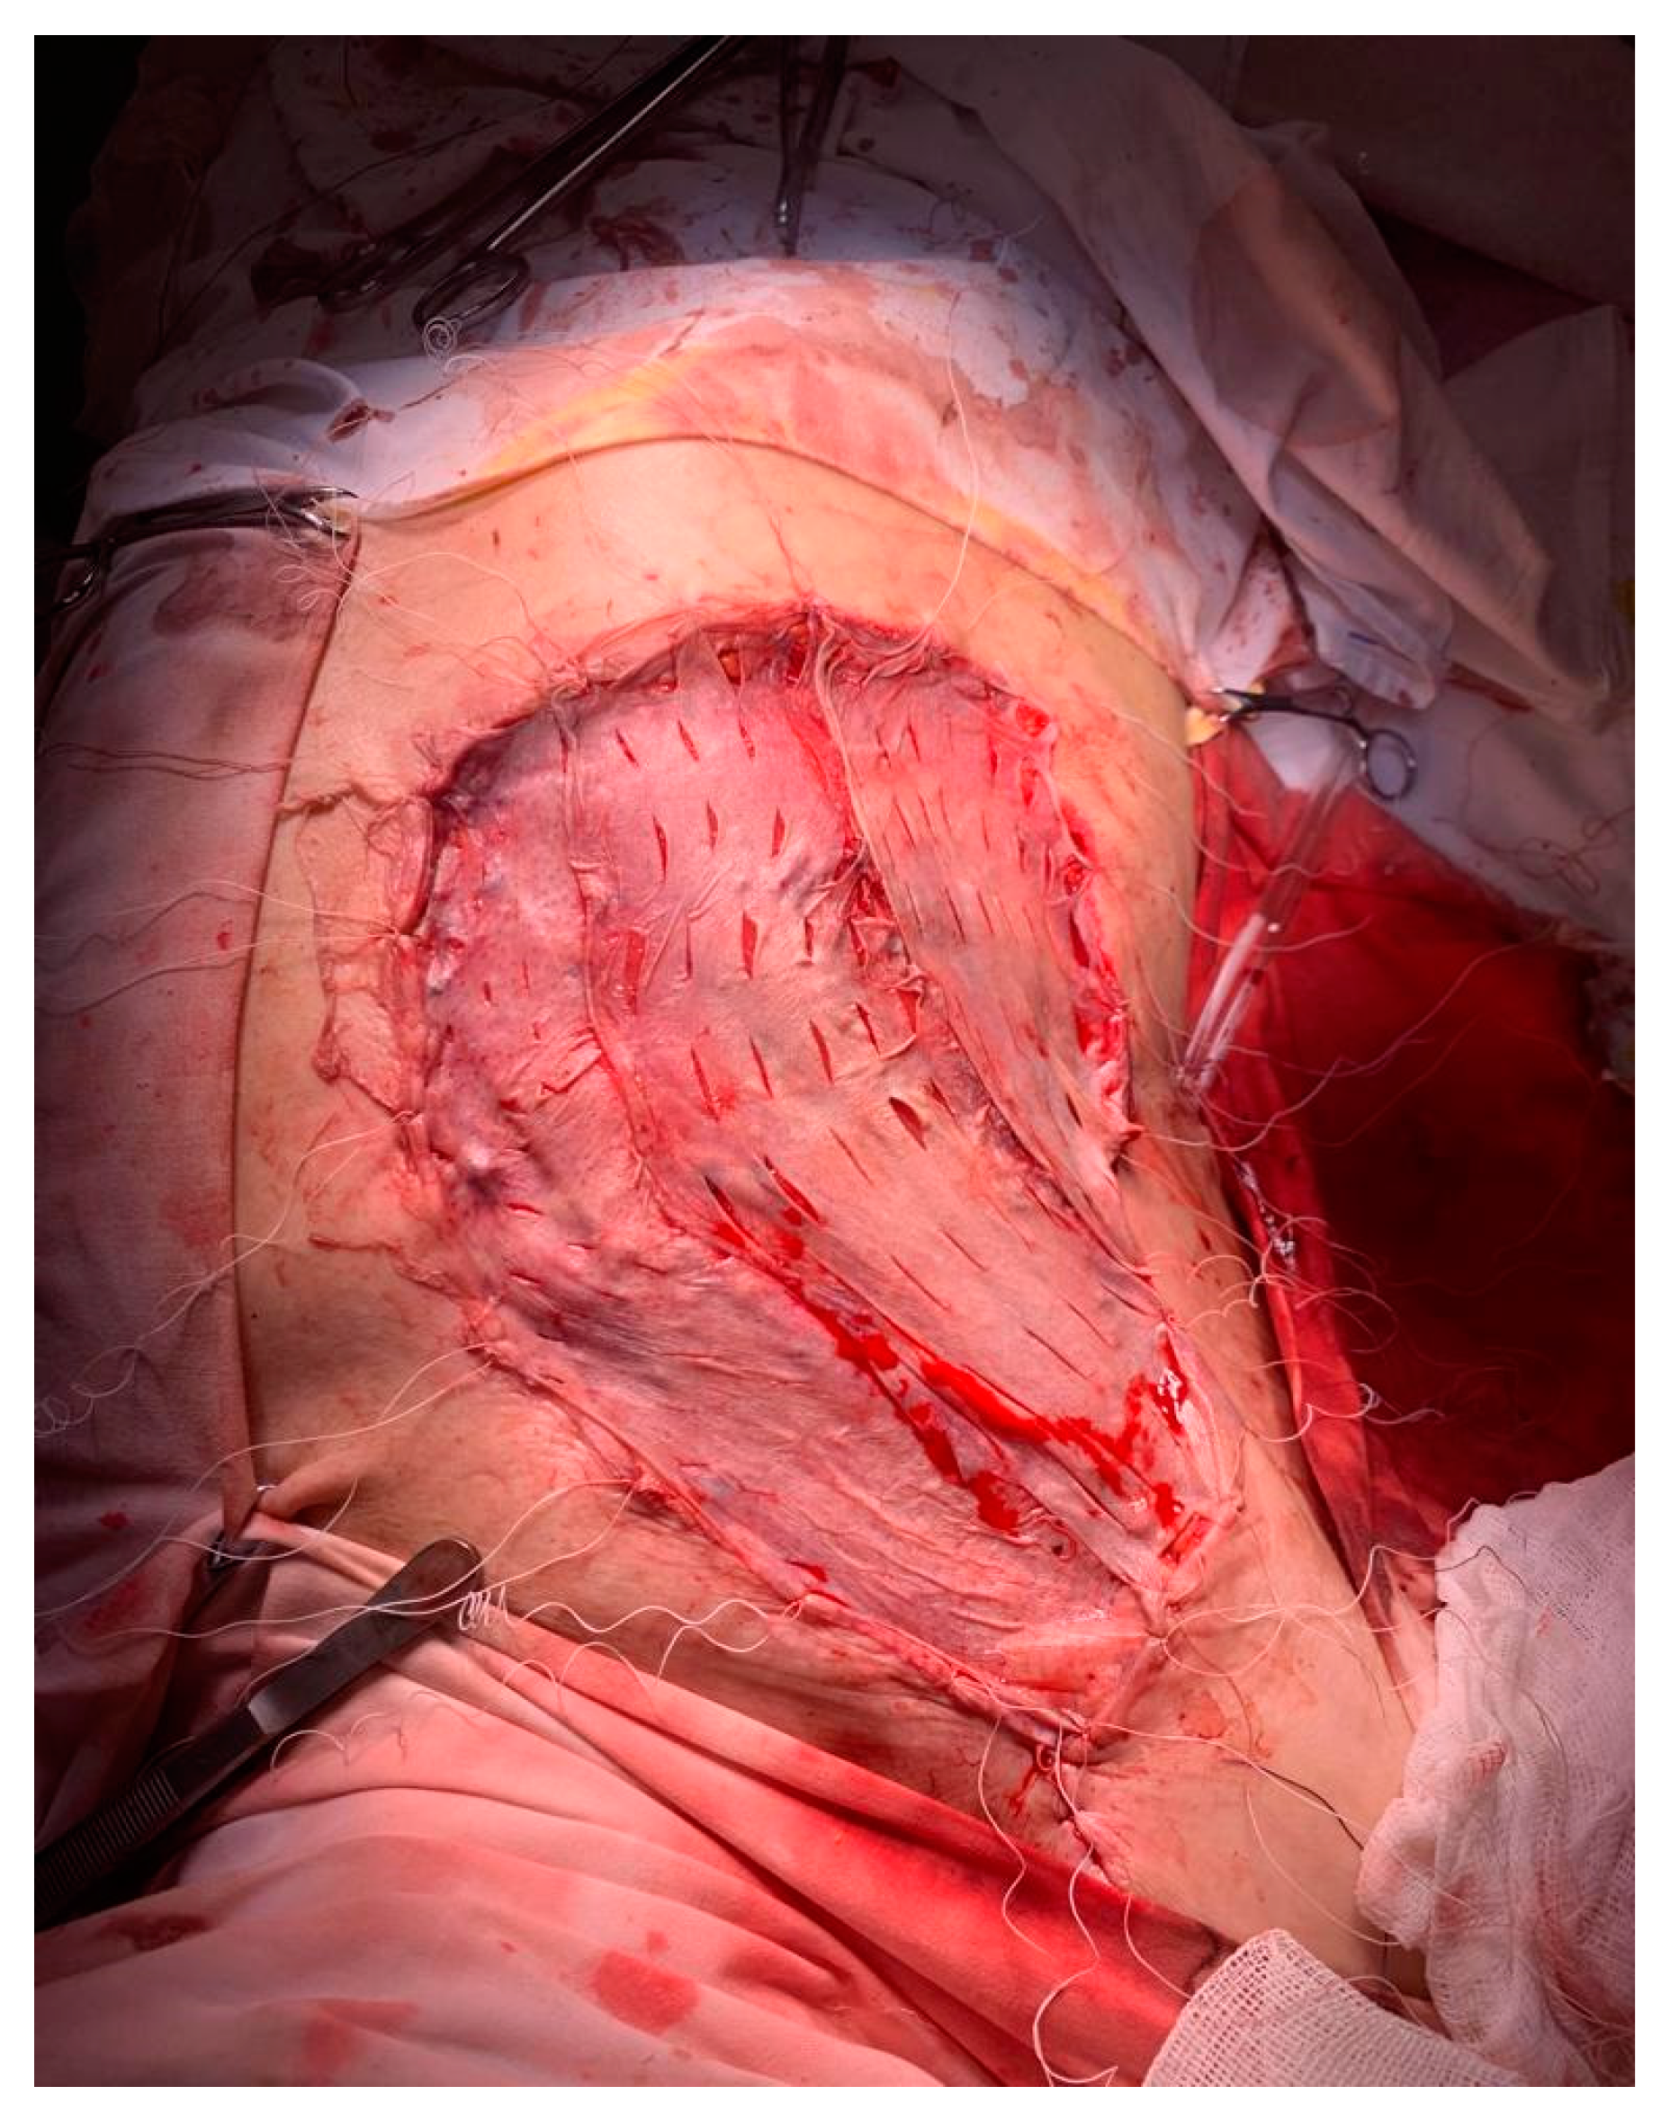

2. Case Presentation